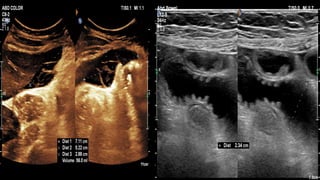

This document discusses the evaluation of right lower abdominal pain and lists appendicitis as a key cause. It notes that other potential causes include hemorrhagic cysts, heterotrophic pregnancy, salpingitis with pyosalpinx, funiculitis, and torsion of an undescended testis. The document was presented by Dr. A.S.M. Sufian of Cumilla Medical College Hospital and thanks the audience for their patience and listening.